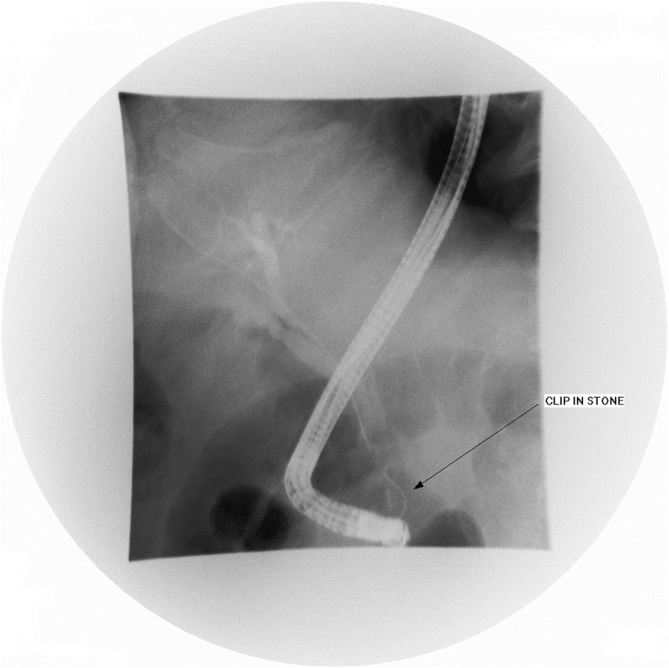

Three days following admission, the patient developed cholestatic jaundice and fever. Liver biochemistry showed the following values: total bilirubin 48 gm/dl (N: <21 gm/dl), gamma-glutamyl transferase 771 U/L (N: 8–61 U/L), alkaline phosphatase 140 IU/L (N: 40–129 IU/L), aspartate aminotransferase 175 IU/L (N: 10–40 IU/L), and ALT 182 U/L (N: 8–41 U/L). The patient was transferred to a specialized endoscopy centre. Urgent ERCP revealed a solitary mid-CBD filling defect encasing a linear metallic radiodensity consistent with a gallstone and embedded endoclip (Fig. 3). Medium-sized sphincterotomy was successfully performed, and the stone and clip were extracted using a retrieval balloon catheter (Extractor™ Pro RX, Boston Scientific, Cork, Ireland) and released into the duodenum (Fig. 4). Gross examination of the stone revealed a closed endoclip.

Diagnosis of ECM requires high index of clinical suspicion and is frequently made at the radiological level. Serial abdominal radiographs and cross-sectional imaging can prove helpful in detecting early displacement of endoclips, and the term “cat’s eye calculus” is often used to denote the endoclip-stone appearance on CT scan [ref. 15]. ERCP remains the gold standard to confirm the diagnosis and along with sphincterotomy offers the best treatment modality with success rate of 85% [ref. 2]. Both balloon catheter or wire basket can be safely used for endoclip-stone retrieval. Surgical exploration and percutaneous transhepatic cholangiography should be reserved as rescue procedures for cases in which endoscopic therapy is either not feasible or fails [ref. 16]. The latter could be due to the unfavourable endoclip-stone orientation within the CBD or the presence of biliary strictures, fistulas, or large stones [ref. 2,ref. 17].